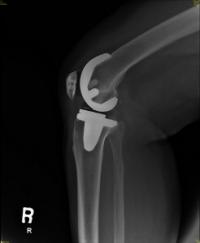

¹«´õ¿î ³¯¾¾¿¡ °üÀý¿° ¾ÇÈ, ¡®Àΰø°üÀý ġȯ¼ú¡¯·Î ±Øº¹

[¿Óóµ¥Àϸ®] ¿©¸§ÀÌ ÄÚ¾ÕÀ¸·Î ´Ù°¡¿Ô´Ù. »ç½Ç»ó ÀÌÁ¦ ¿©¸§ÀÌ ½Ã...